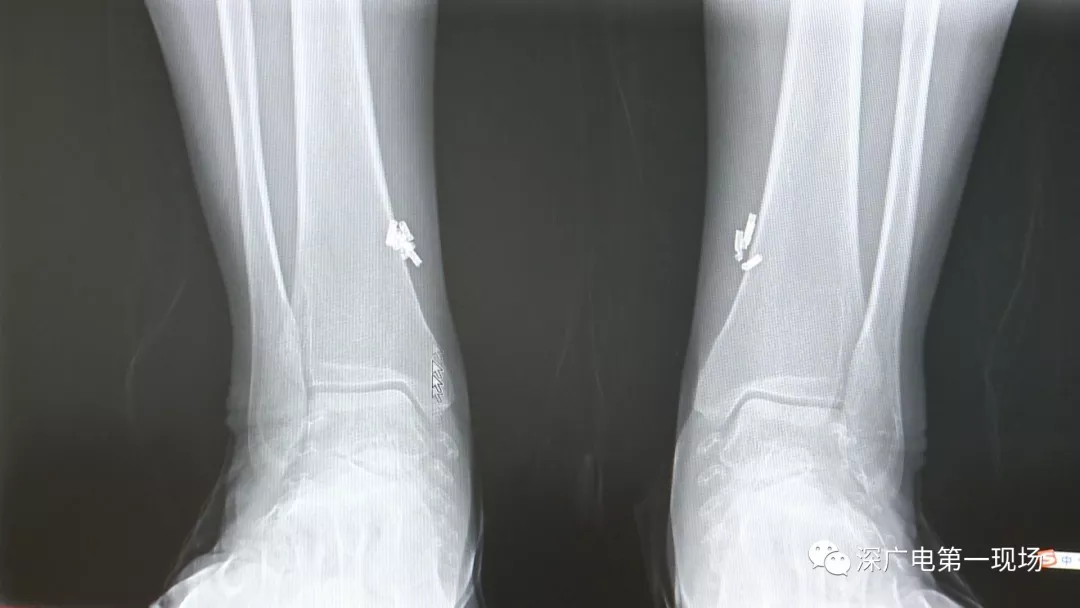

深圳一女子全身被植入彈簧圈,數(shù)量多到驚人!竟是為治這病…

出于保護(hù)患者,我們沒有直接采訪,但是通過醫(yī)生的介紹,記者了解到,病人是個36歲的女性,2歲開始就有癲癇病史,而且藥物治療也并不見效。

多方打聽之后,在山東某診所用全身埋彈簧圈的方式治療癲癇。陶主任介紹,這樣的方式想要治愈,那幾率也等同于撞大運(yùn)??!